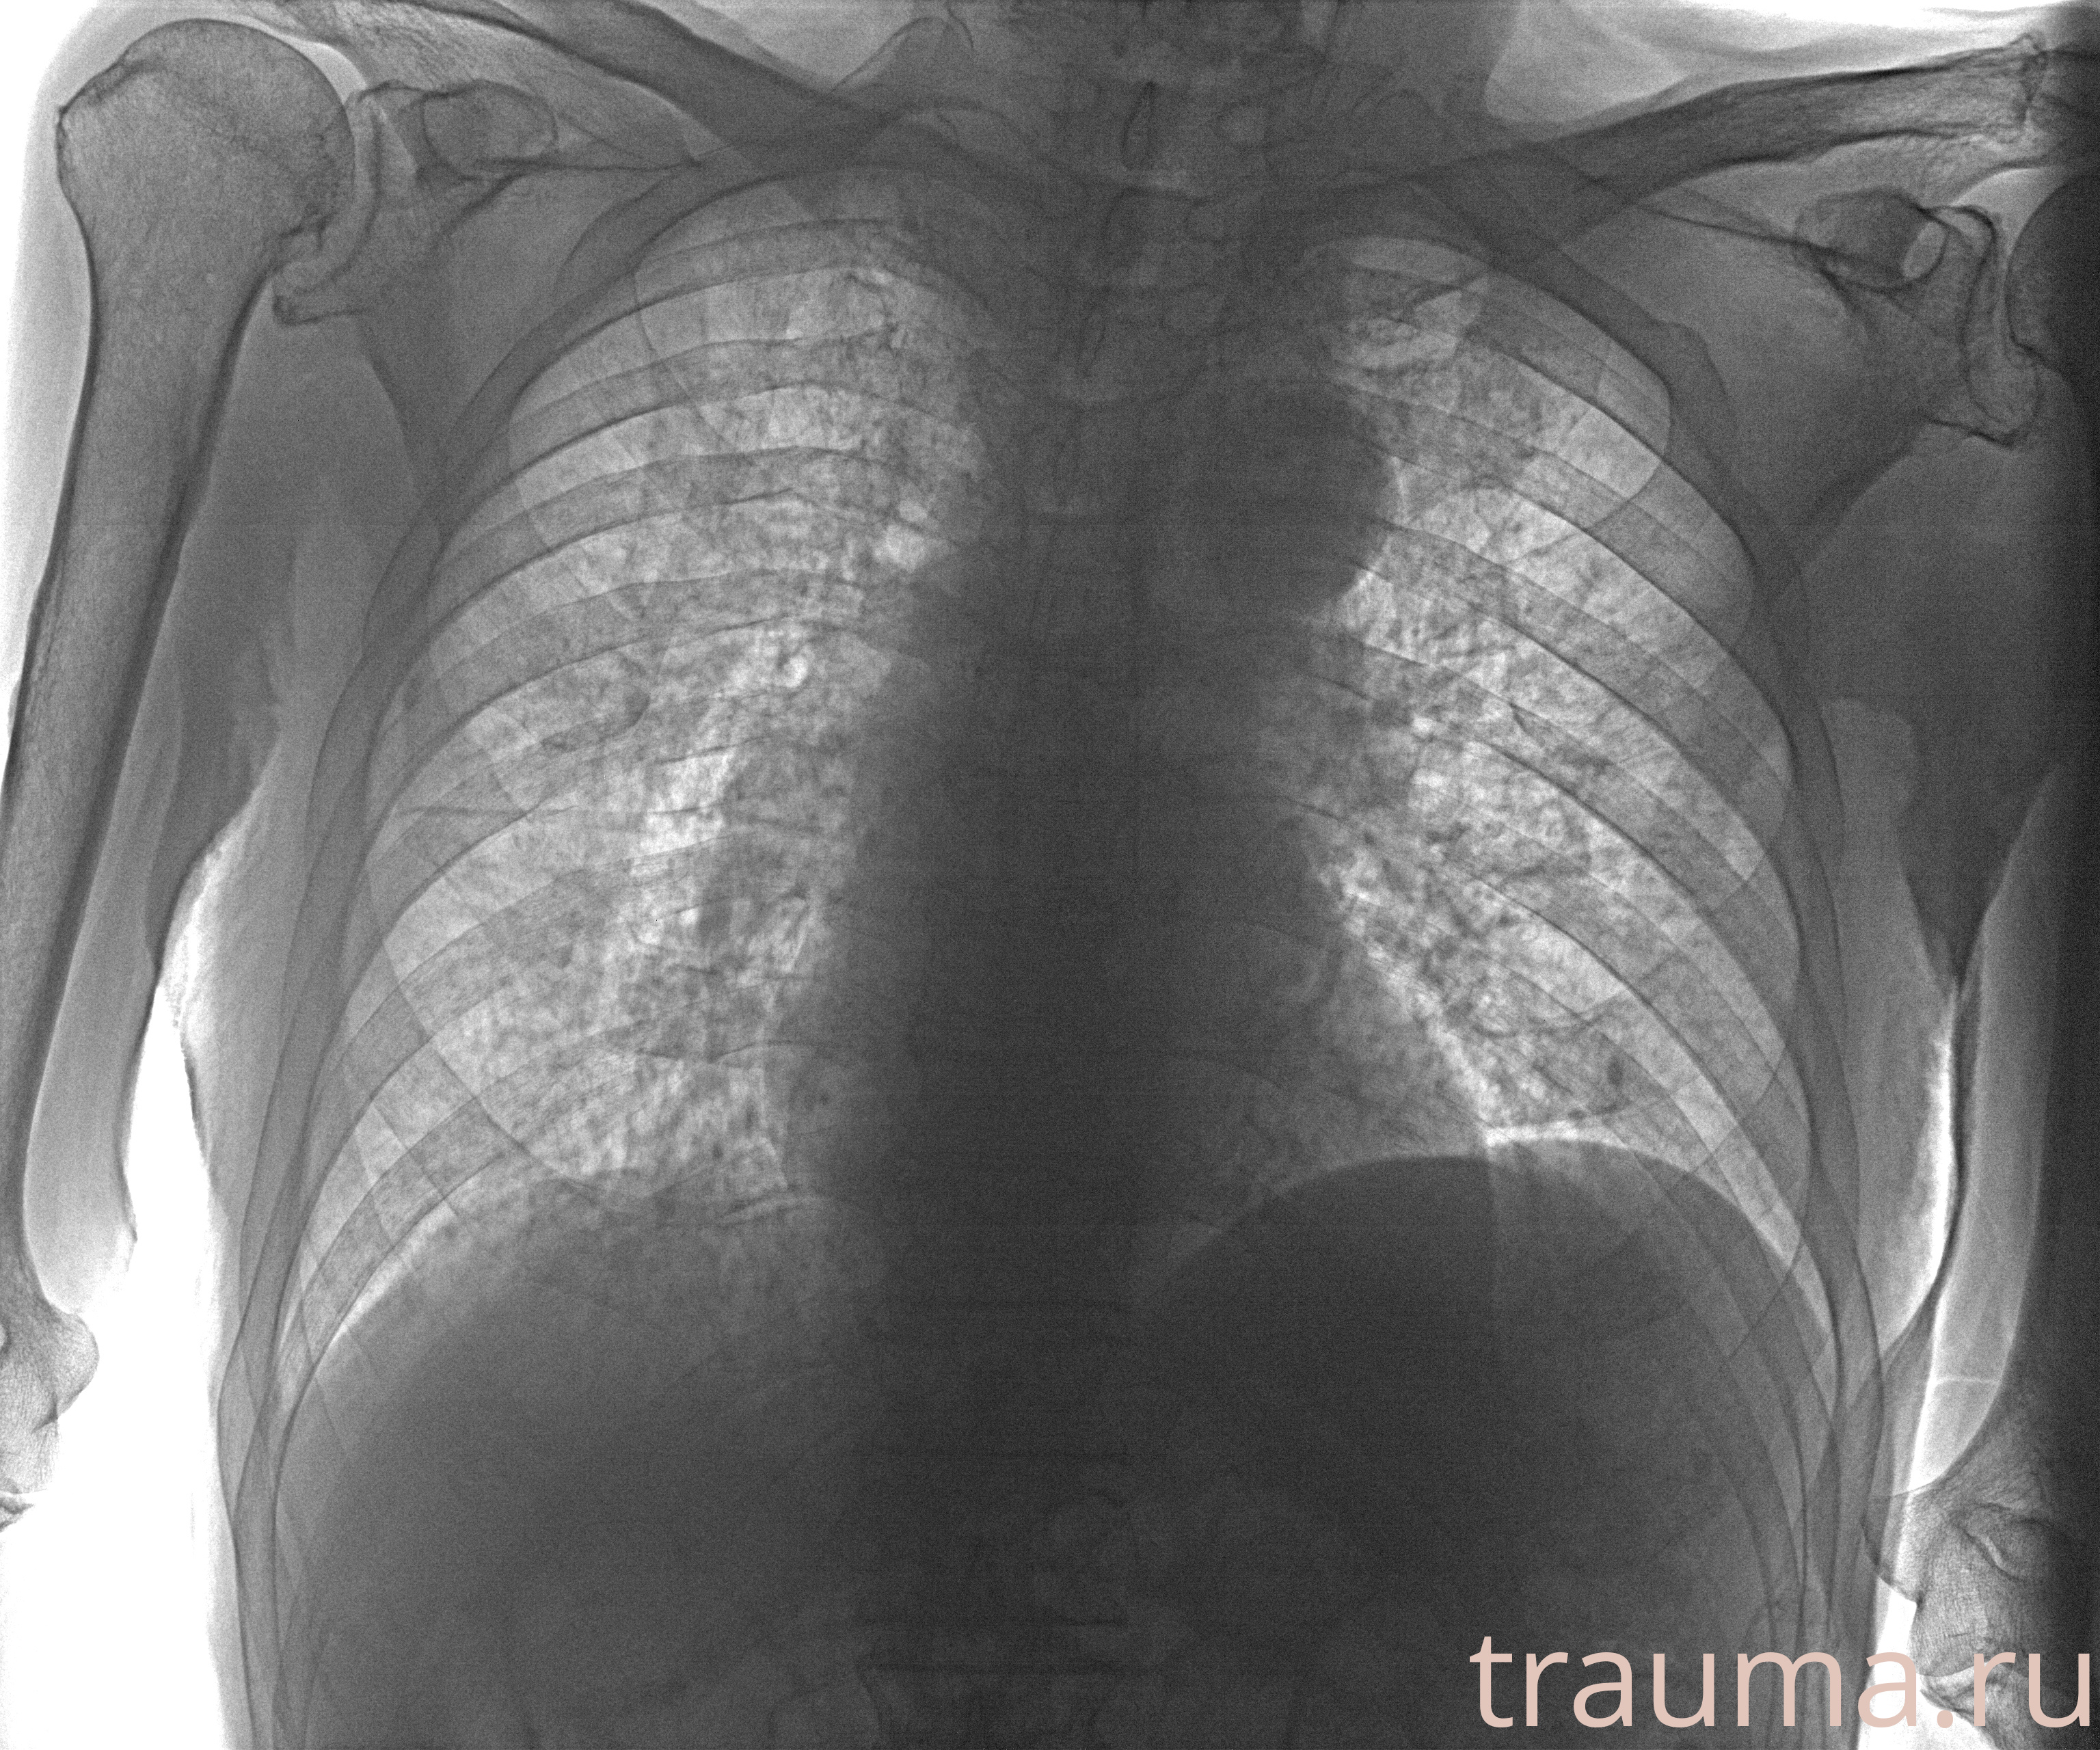

Рентгенограммы

Рентген на дому: по вашему адресу приезжает врач-рентгенолог, травматолог-ортопед с мобильным рентгеновским аппаратом, проводит диагностику травмы или заболевания, делает необходимые рентгенограммы, дает рекомендации по дальнейшему лечению. Получить качественные снимки в домашних условиях возможно благодаря уникальной методике, разработанной МосРентген Центром для института  Склифосовского